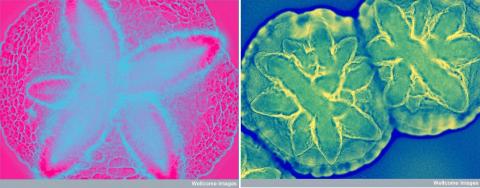

치주염을 일으키는 대표적 박테리아인 아그레가티박터 액티노마이세템코미탄스(Aggregatibacter actinomycetemcomitans) 현미경 사진 Credit : Wellcome Images / flickr

연구팀은 치주질환과 관계된 여러 박테리아 중에서 A.액티노마이세템코미탄스가 호중구의 과시트룰린화를 유도할 수 있는 유일한 병원균이라는 사실을 발견했다. 호중구는 면역 백혈구의 하나로 시트룰린화에 필요한 효소인 펩티딜아르기닌 데이미나제(PAD)가 매우 풍부하다. 연구팀에 따르면 호중구는 류머티즘 관절염과 치주질환을 동시에 가진 환자의 관절과 치주에서 가장 많이 발견되는 염증 세포로, 여러 해 동안 류머티즘 관절염에서 나타나는 과시트룰린화의 주요 원천으로 연구돼 왔다.